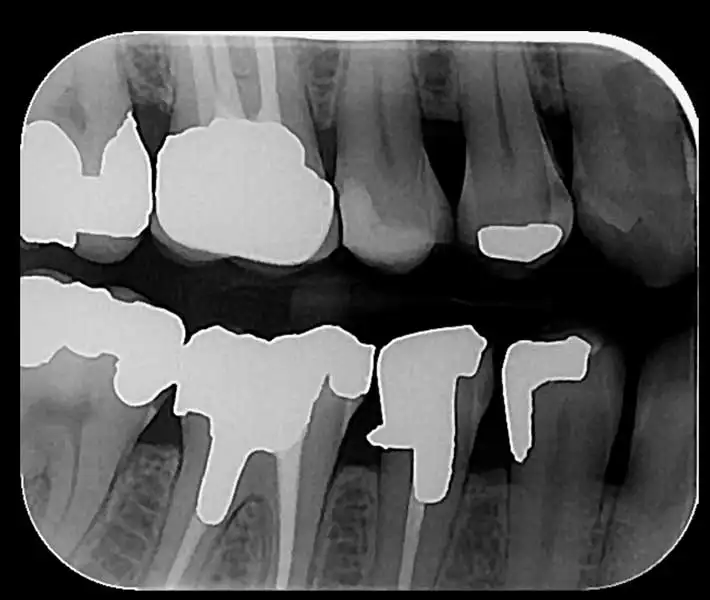

- رادیوگرافیهای داخل دهانی (پری اپیکال ،اکلوزال ،بایت وینگ)